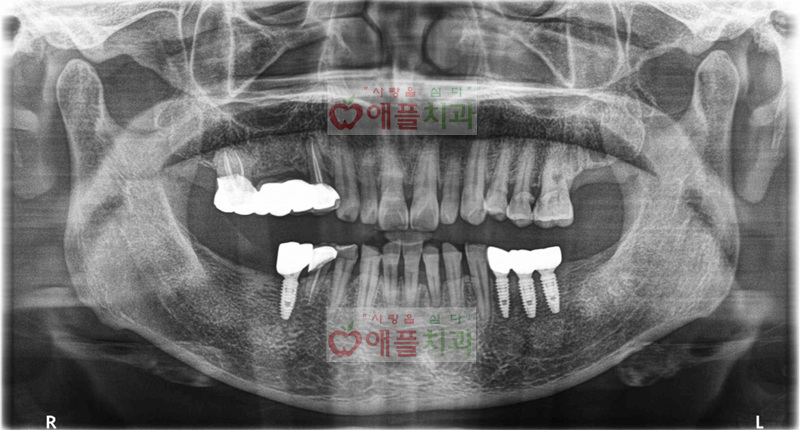

< 네비게이션을 이용한 임플란트 치료 완료>

당일날 좌측 3개 우측 1개의 임플란트를 식립하였습니다. 수술 후 2주째 실밥제거하러 오셨을때, 크게 아프지 않고 붓지도 않았다고 하십니다.

네비게이션 임플란트의 또 장점은 내원 횟수가 줄어듭니다. 바쁘신 와중에 멀리서 내원하신 분들에게는 더욱 만족하십니다.

임플란트 수술후 2.5~3개월째 정상적인 식사가 가능한 최종 보철물이 완성됩니다.

현재까지 별탈없이 만족하시면서 사용하고 계십니다.

3~4개월 주기로 내원하시어 애플치과에서 꼼꼼히 관리 해드리고 있습니다.